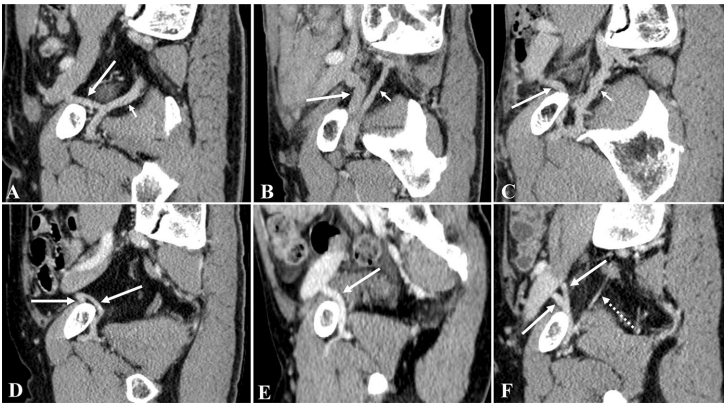

为突破这些局限,张静、黄俊林等研究团队在《Scientific Reports》发表了这项基于CT血管成像的大样本研究。研究人员收集了2018-2024年间719例(1438侧)接受全腹/盆腔CT检查患者的影像数据,采用GE 64排CT进行动脉期和门静脉期双期扫描,通过多平面重建(MPR)、最大密度投影(MIP)和容积再现(VR)等技术,由两位资深放射科医师独立评估CMOR的发病率、血管直径、解剖构型等指标。研究特别建立了标准化的命名体系:异常闭孔动脉(AOA)、异常闭孔静脉(AOV)、血管吻合(VA)等术语均明确定义,并创新性地采用"异常血管+吻合方式+正常血管"的复合命名法。

静脉死亡冠(VCMOR)的发病率与解剖构型

这项研究最突出的贡献在于对VCMOR的系统分类。68.43%患者存在VCMOR,共识别出14种解剖构型,根据髂内外静脉系统间是否存在血管吻合分为两大类型:无血管吻合型(20.75%)包含5种亚型,以单纯AOV最常见(61.45%);存在血管吻合型(79.25%)包含8种亚型,其中AOV+VA+OV构型占比高达81.39%。研究首次发现VCMOR存在三种回流路径:直接汇入髂外静脉(EIV)占主流(756侧),与腹壁下静脉(IEV)共同汇入(83侧),以及单独汇入IEV(16侧)。

动静脉复合型死亡冠

17.39%病例同时存在ACMOR和VCMOR,右侧发生率显著高于左侧。值得注意的是,79.07%的ACMOR患者伴有VCMOR,提示临床发现动脉变异时应高度警惕静脉变异。